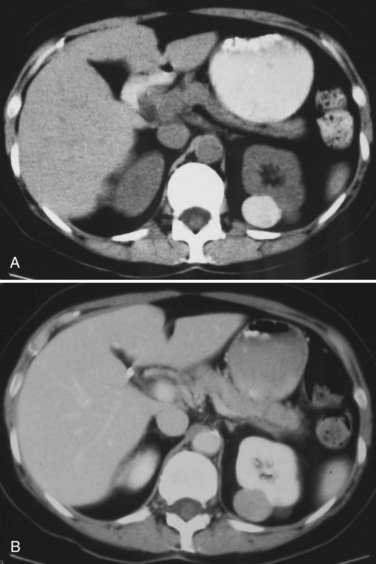

Category II lesions are minimally complex cysts that are generally benign but have some radiologic findings that cause concern (Fig. 49–5). These lesions include septated cysts, cysts with calcium in the wall or septum, infected cysts, and hyperdense (high-density) cysts (Bosniak, 1997; Israel and Bosniak, 2005). Hyperdense cysts are benign lesions that contain old, degenerated, or clotted blood; therefore, the CT attenuation of their contents is increased (>20 HU). Classic hyperdense renal cysts are small (<3 cm), round, and sharply marginated and do not enhance after the administration of contrast material (Fig. 49–6). This category has now been subdivided to differentiate category II lesions that do not require surveillance from category IIF lesions that mandate surveillance. The nuances involved in this classification are highlighted in Table 49–3. High-quality imaging, preferably CT, and considerable radiologic expertise are required to optimize the characterization of complex renal cystic lesions. The risk of malignancy for category IIF renal cysts is 5% to 10%, and these lesions should be observed with periodic renal imaging (Kausik, 2002; Israel and Bosniak, 2003b, 2005).

Figure 49–5 Bosniak class II renal cysts. A, CT scan shows right renal cyst with thin internal septation. B, CT scan in another patient shows relatively thin, curvilinear calcification in the septa of the wall of right renal cyst.

(Courtesy of Dr. Terrence Demos, Maywood, IL.)

Figure 49–6 Bosniak class II hyperdense cyst. A, Unenhanced CT scan shows small, smooth-walled, high-density left renal cyst. B, CT scan after administration of contrast material shows no enhancement of the cyst. This is an extreme example of a hyperdense cyst.